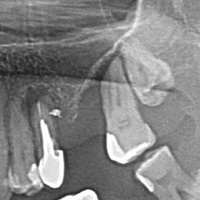

Pacjent z bólem, nieudana próba udrożnienia kanałów pod mikroskopem. Decyzja o resekcji korzenia policzkowego dalszego. RTG kontrolne rok po zabiegu.